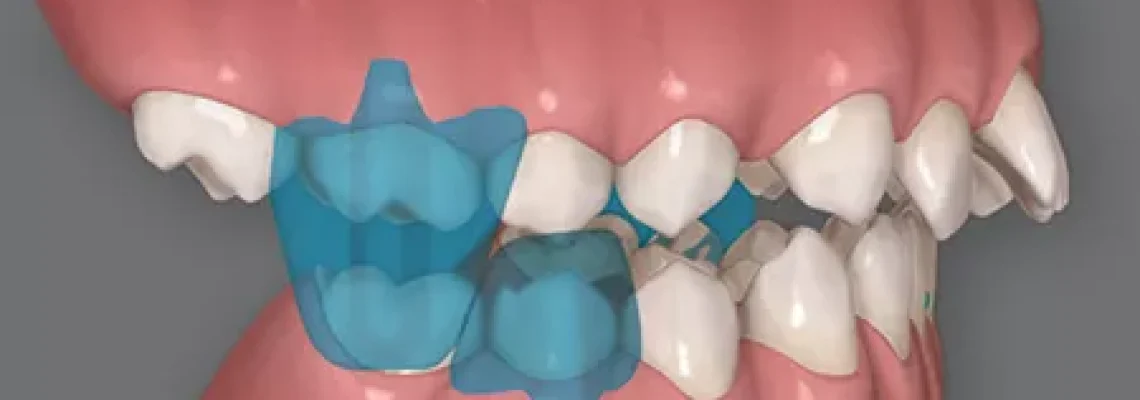

Objetivo: Relatar o caso clínico de uma paciente com má oclusão de Classe II esquelética e dentária, com trespasse horizontal acentuado. Caso clínico: Após avaliação dos elementos diagnósticos, avaliação clínica e facial, optou-se por um

tratamento com avanço mandibular e distalização de molares superiores.

Os alinhadores Invisalign foram o recurso utilizado para essa correção. Foram planejadas duas etapas, a primeira com as Precision Wings para o movimento ortopédico, e

a segunda etapa com distalização sequencial e uso de elásticos de ancoragem de Classe II.